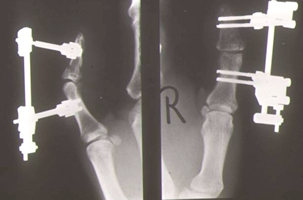

Endgliedtrümmerfraktur des Daumens - Ergebnis nach geschlossener Reposition

Trümmerfraktur des Daumenendgliedes. Alleiniger Zug am Finger ohne Eröffnung der Haut ermöglichen die gelenküberbrückende Stabilisierung mit einem Minifixateur.